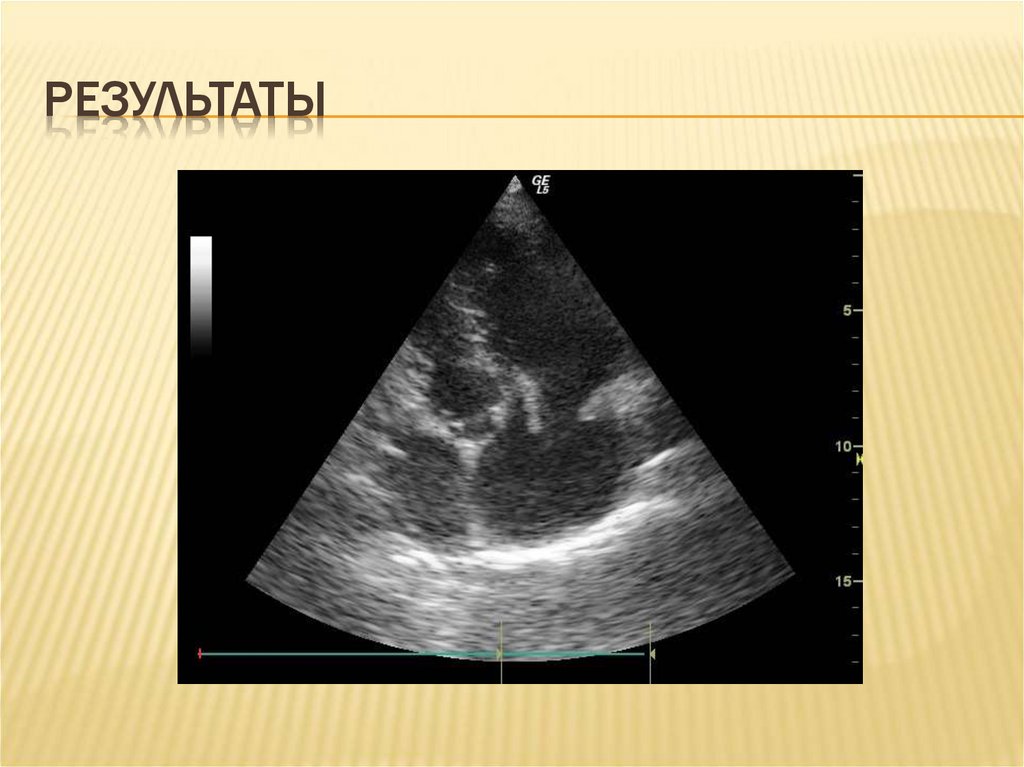

13. результаты

РЕЗУЛЬТАТЫ

14. результаты

22. Особенности эхокардиографического описания

ОСОБЕННОСТИ ЭХОКАРДИОГРАФИЧЕСКОГО

ОПИСАНИЯ

1.

2.

3.

4.

5.

Возраст вегетации (до двух недель, свыше

двух недель, с элементами организации)

Размер и площадь вегетации (до 2 см и

более 2 см в диаметре)

Вероятность отрыва (флотирующие,

соприкасающиеся вегетации)

Перегрузка правого желудочка

Поражение миокарда и перикарда